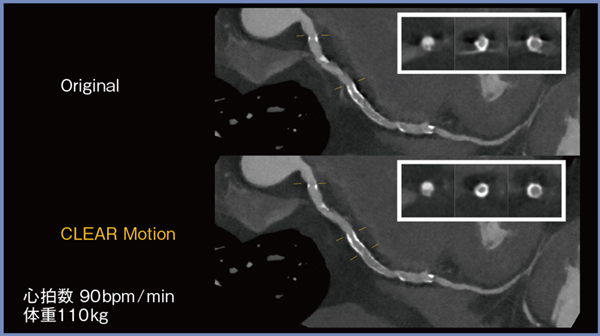

図6はHR:90bpm,体重110kgの症例であるが,CLEAR Motionを適用したことでステントから発生するアーチファクトが大幅に低減し,明瞭な画像が得られている。

図6 CLEAR Motionによる高心拍・高体重患者のステントの描出の改善(短軸像)